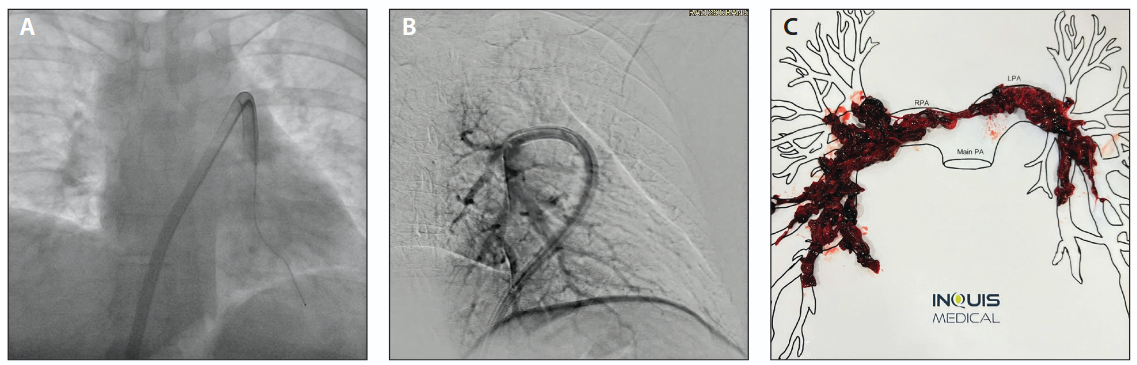

The AVENTUS Thrombectomy System was selected for thrombectomy of both the right and left pulmonary arteries. Starting with the right side, the catheter was introduced via the femoral vein and advanced over a Hi-Torque Supra Core (Abbott) guidewire using the system’s integrated 4-F guide catheter, allowing for efficient navigation through the dilated right ventricle to the right pulmonary artery (Figure 3). The integrated dilator tip and directional aspiration eliminated the need for any dilator or catheter exchange before the initial aspiration. Initial aspirations successfully removed the clot, and the catheter was advanced and rotated to target the truncus for additional aspirations, which removed most of the clot on the right side. Navigating to the left side was achieved by simply retracting the catheter and redirecting the integrated wire and guide catheter into the left pulmonary artery (Figure 4A). The catheter was then advanced into the left lower posterior lobe. Aspirations were performed to remove clot from the left side, and a final angiogram was taken (Figure 4B). After each aspiration, blood and clot collected in the aspiration syringe was transferred into the blood filtration chamber by simply depressing the syringe plunger. The one-way valve integrated into the syringe tip automatically diverts the flow into the blood filtration chamber for filtration and return to the patient. Immediate postprocedure improvements included a reduction in right atrial pressure from 20 to 15 mm Hg and a drop in pulmonary artery pressure from 60/24 to 30/20 mm Hg.

Figure 4. Advancement of the AVENTUS system to the left pulmonary artery (A), performed without a need for wire, navigation tool, or catheter exchange. Selective angiogram of the left lower lobe showing resolution of large thrombotic burden (B). Thrombus composition suggests element of subacute and acute thrombi (C).